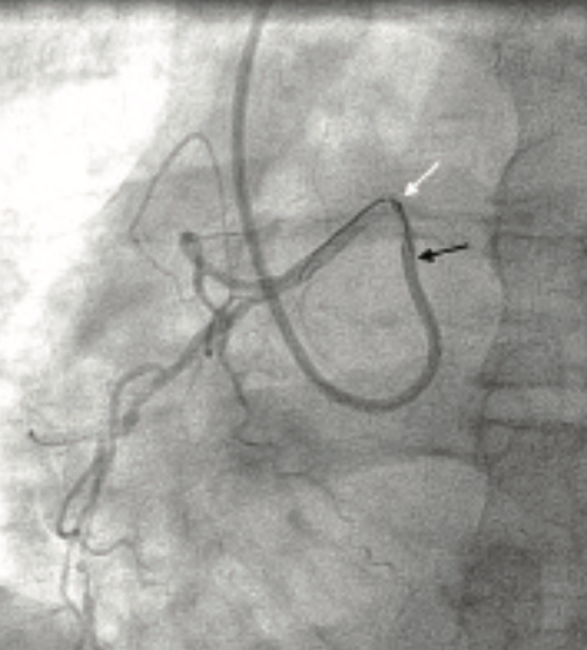

Case #2: The Need for a Guide Catheter Extension: Percutaneous Coronary Intervention of a Diffusely Diseased Anomalous Right Coronary Artery

A 62-year-old male with a history of medically managed non-ST segment elevation myocardial infarction (NSTEMI) in 2014, hypertension, hyperlipidemia, and a former smoker presented to the hospital with a sudden onset of worsening substernal chest pain and shortness of breath of one-day duration. He had been admitted for an NSTEMI 4 years prior, with the culprit lesion being an anomalous high take-off of the right coronary artery (RCA) from the left coronary cusp. Intervention had been attempted on the RCA lesion. Multiple guide catheters had been used to engage the RCA. Although the wiring was performed without ostial engagement with the guide catheter, medical management was deemed appropriate, due to the infeasibility at that time of passing coronary balloons and stents. At his current presentation, the patient noted off-and-on chest tightness and shortness of breath over the past two months, and a history of cough and chills of a 1-week duration. Physical examination revealed a temperature 97.6˚F, heart rate of 71 beats/min, blood pressure 119/77 mmHg, and oxygen saturation 95% on 2 L/min through a nasal cannula. The remaining physical examination was unremarkable, except for faint bilateral crackles on auscultation. Lab work revealed a peak troponin I of 12.28 (reference range: 0.00-0.03 ng/mL) and brain natriuretic peptide (BNP) of 398 pg/mL (reference range: 0-100 pg/mL). His electrocardiogram revealed 1.0 mm ST-segment depressions in leads V4 through V6, and non-specific T wave flattening in the lateral precordial and limb leads (Figure 1). A computed tomography angiogram of the chest revealed a right upper lobe consolidation and no evidence of acute pulmonary embolism. An echocardiogram showed a normal left ventricular ejection fraction of 54% and inferior akinesis. After the diagnosis of right upper lobe pneumonia, the patient was started on broad-spectrum antibiotics.